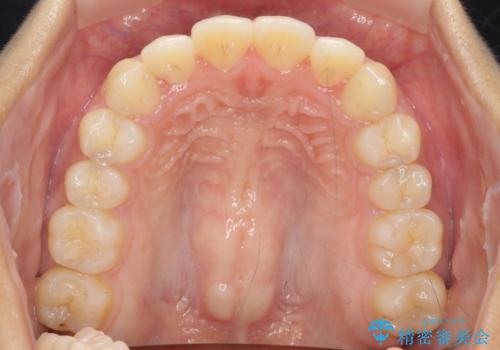

ワイヤー部分矯正を併用して治療期間を短縮 マウスピース矯正治療

- 前歯のガタつき、上下たがい違いになっている歯並び(クロスバイト)の改善を求めて来院されました。

インビザラインによる矯正治療を行いますが、クロスバイトの改善をワイヤー部分矯正で事前に行うことにより治療期間の短縮する治療計画を立案します。

上下すれ違った噛み合わせはマウスピースでは改善に時間がかかり、またねじれが残ってしまうことも多々見られます。

マウスピース矯正を行う前に、これらの症状の改善の得意なワイヤー部分矯正を行うことで治療期間を短縮し、確実にすれ違いを改善することができます。